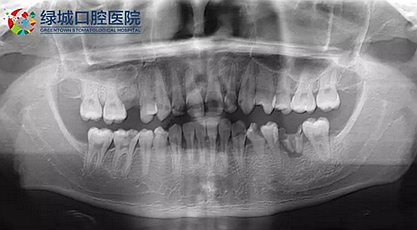

我們的主人今年才25歲,可卻從很小的時候就嗜好喝可樂等碳酸飲料,幾年下來,讓我們兄弟姐妹們整天浸在碳酸里受這蝕骨之痛,原本皎潔的外貌如今早己經是腐蝕不堪、丑陋無比,更有甚者,一些兄弟姐妹們已經病入膏肓,被病痛折磨奄奄一息。

下面是醫(yī)生眼中和ct下的我們

一身病痛啊

牙結石、牙齦炎癥、牙體殘缺、慢性牙髓炎、蛀牙......

才二八芳華的我們

已經滿目蒼夷